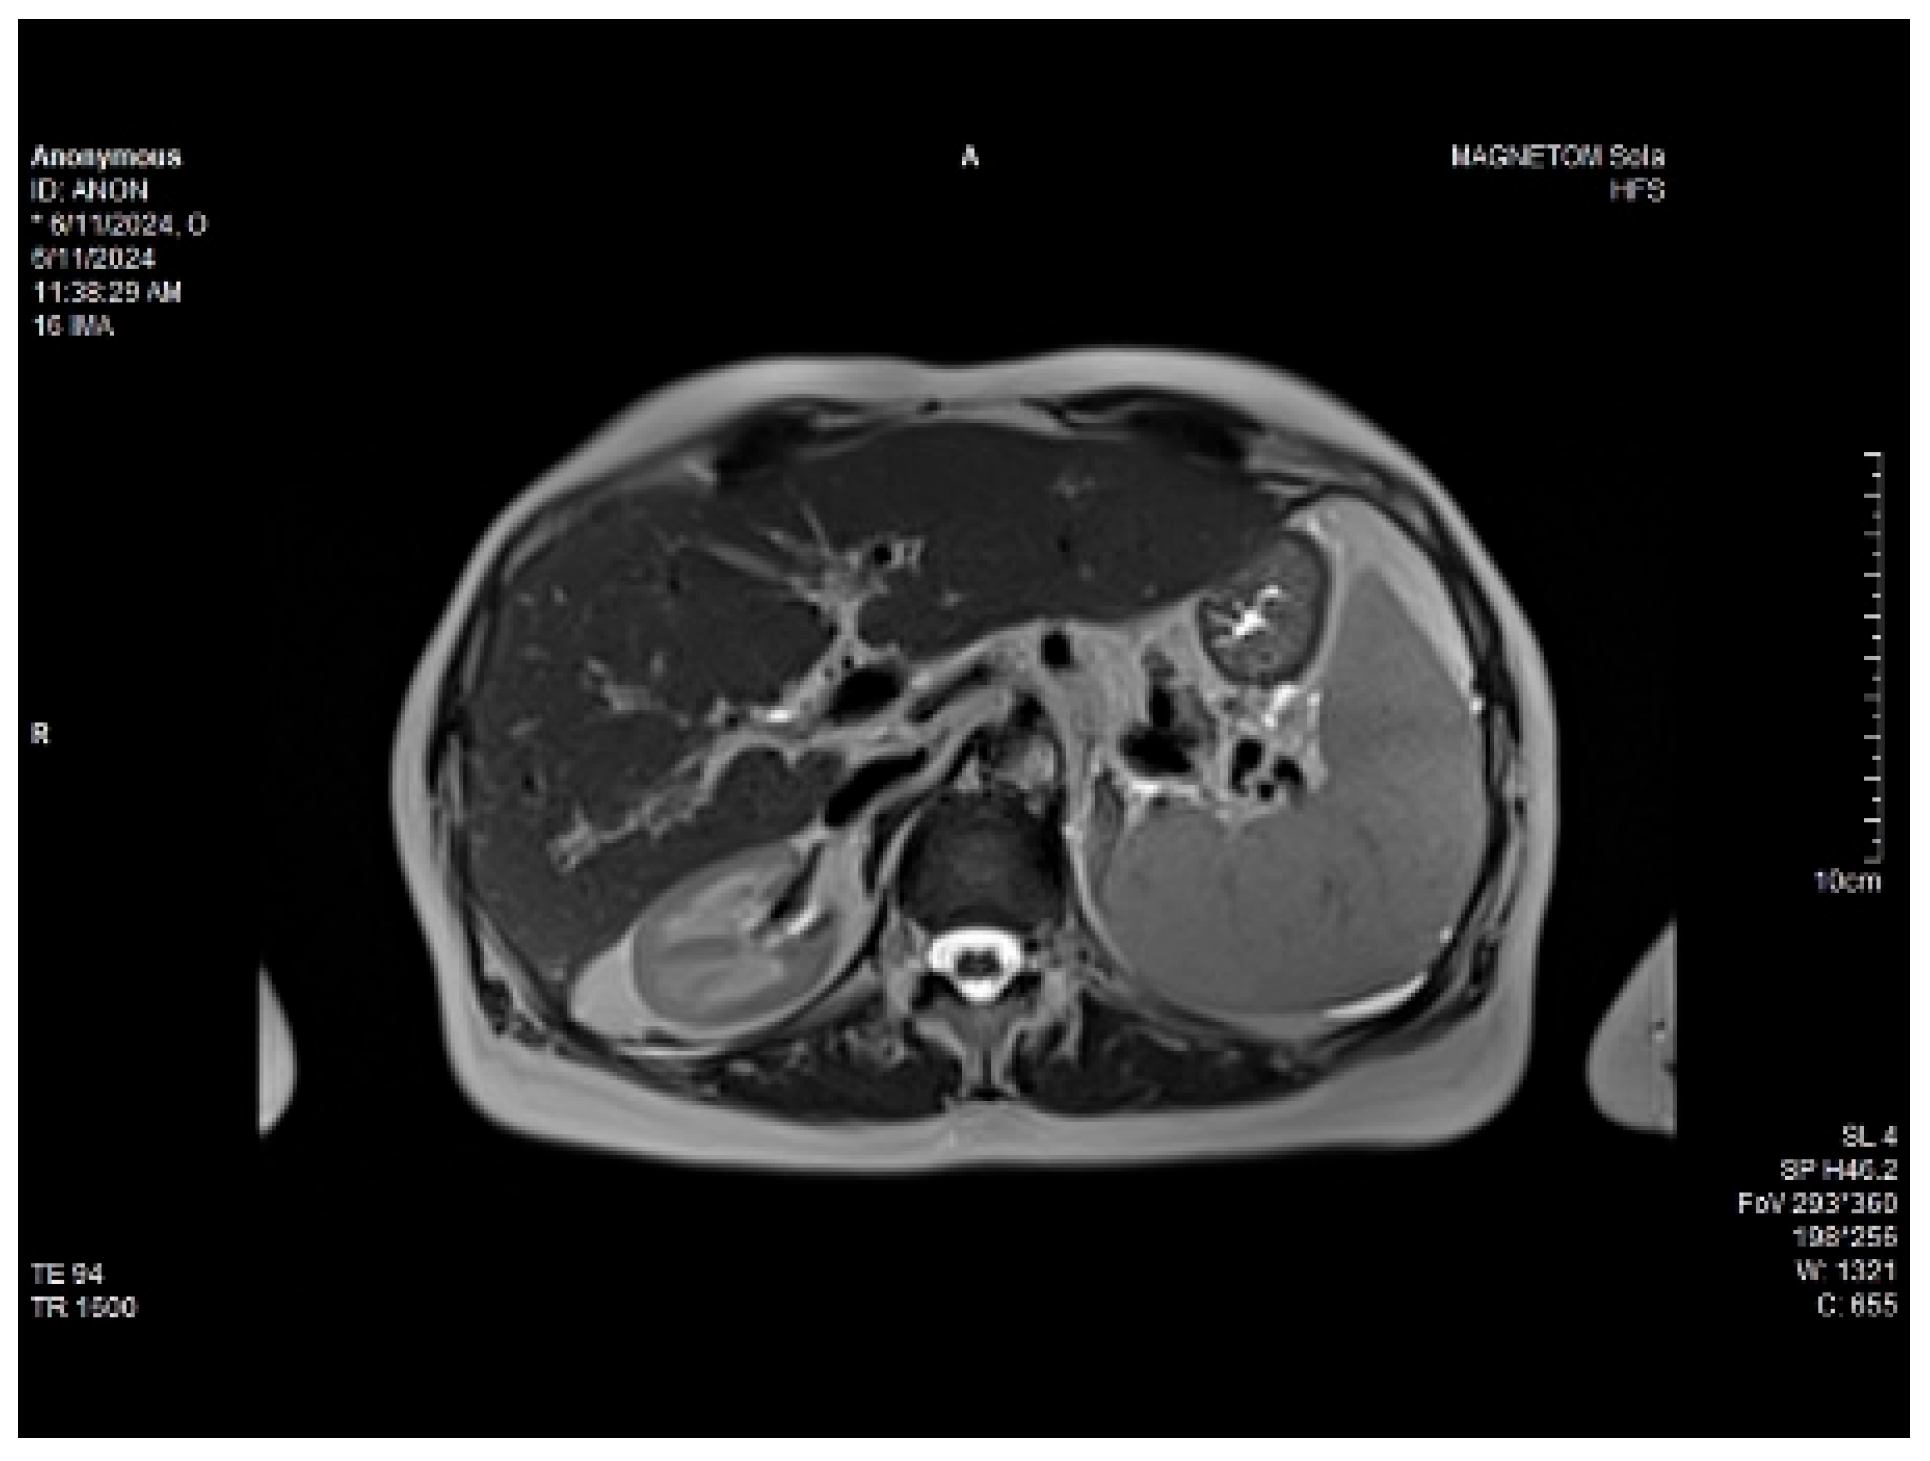

On physical examination, a mild tenderness of the right upper abdominal quadrant, a firm hepatomegaly, a palpable inferior pole of the spleen and a slight increase in abdomen volume were found. No other liver stigmata were noticed. The abdominal duplex ultrasound examination, performed with Siemens high-resolution equipment, showed hepatomegaly with a discrete irregularity of the liver surface, heterogeneity of the liver texture, the caudate lobe at the upper limit, filiform hepatic veins, massive thickening of the gallbladder wall, ascites in small quantity and mild splenomegaly with turbulence of the venous flow in the hilum. The question about liver cirrhosis was asked. Various aspects of the 2D ultrasound examination of the liver are depicted in Figure 2.

Figure 2. The 2D ultrasound aspect of the liver: perihepatic ascites (right,left), caudate lobe at the upper limit (middle).